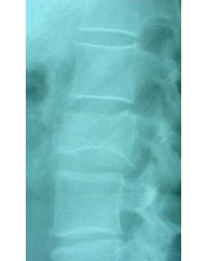

Caso clínico de una resección (corpectomía) y reconstrucción vertebral lumbar en una fractura estallido de nivel L4.